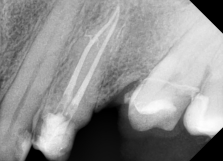

3. Conformación tridimensional segura hasta calibre 25/.04 (secuencia S2) con el sistema R-Shaper

Finalmente, se completó la conformación tridimensional utilizando la secuencia S2 del sistema R-Shaper, alcanzando una preparación apical hasta calibre 25 con conicidad 0.04.

Este sistema mecanizado, diseñado específicamente para anatomías complejas, garantiza una limpieza y modelado eficientes sin comprometer la estructura radicular.

En Calcified Canal Cases con curvaturas severas, el diseño progresivo del R-Shaper minimiza el transporte apical y optimiza la conformación del sistema de conductos, mejorando el pronóstico a largo plazo.